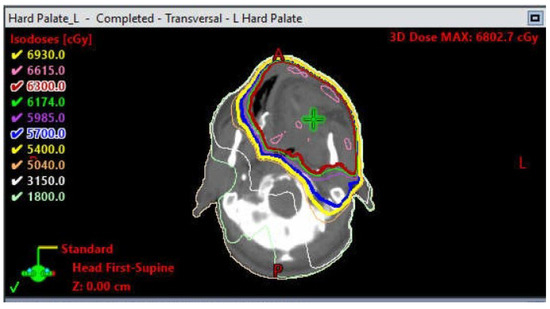

1.4. Osteoradionecrosis

Prevention and Management of Osteoradionecrosis